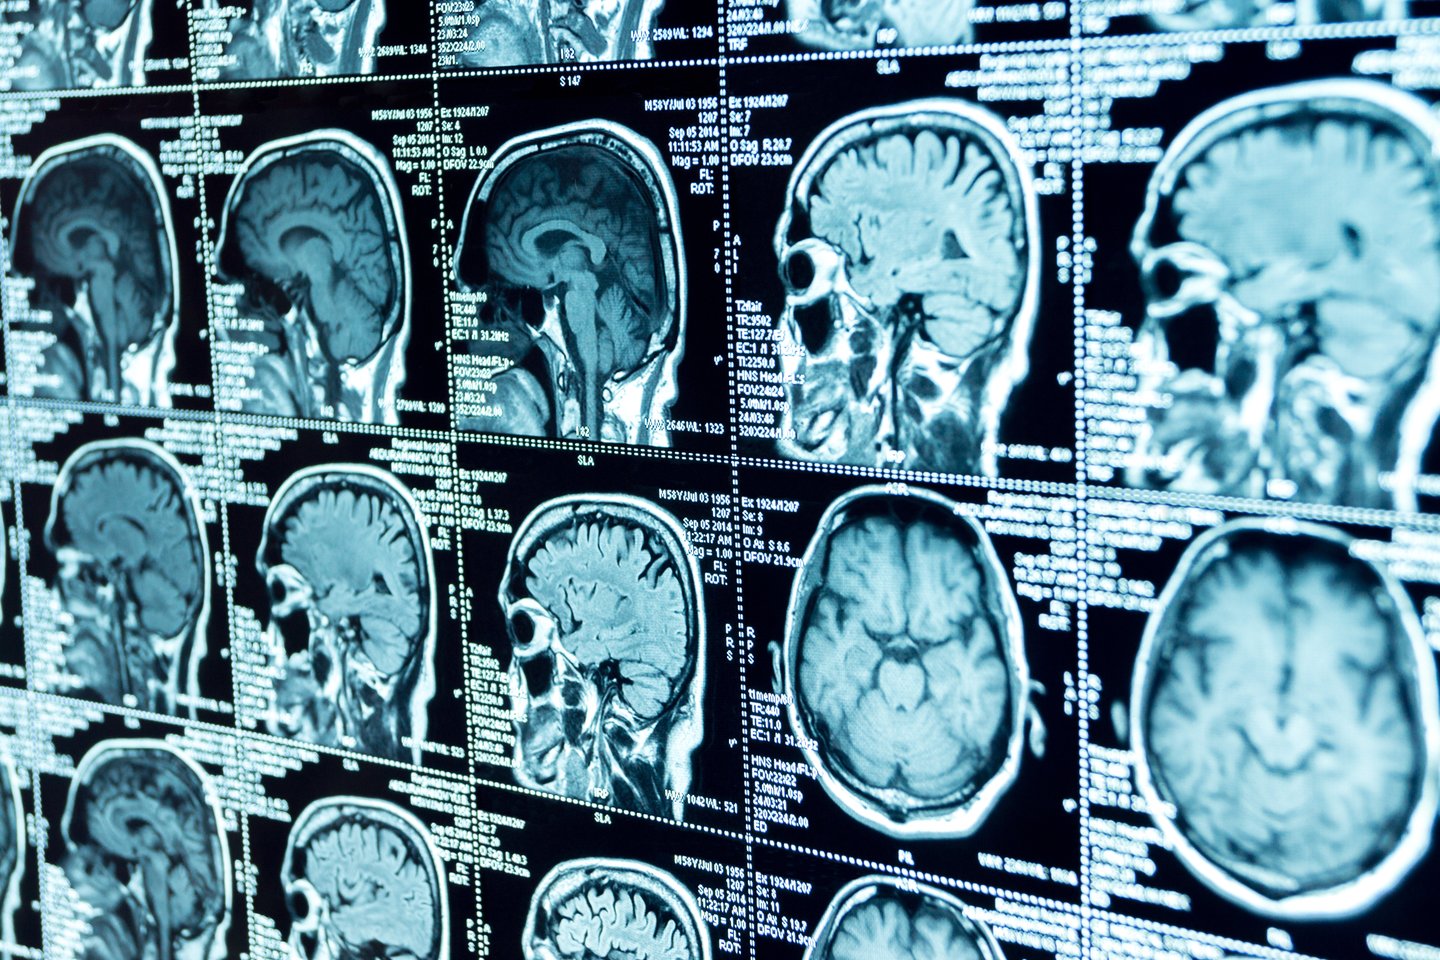

B.Trotmanui taip pat buvo taikoma spindulinė terapija ir chemoterapija. Praėjus daugiau nei dvejiems metams, jo smegenų nuotraukose nematyti jokių vėžio požymių.

„Labai neįprasta turėti tokį vaizdą, ypač kai jam nebuvo atlikta pakartotinė operacija, kuri buvo suplanuota siekiant pašalinti visą auglį“, – paaiškino vyro gydymui vadovaujantis medicinos onkologas dr. Paulas Mulhollandas.